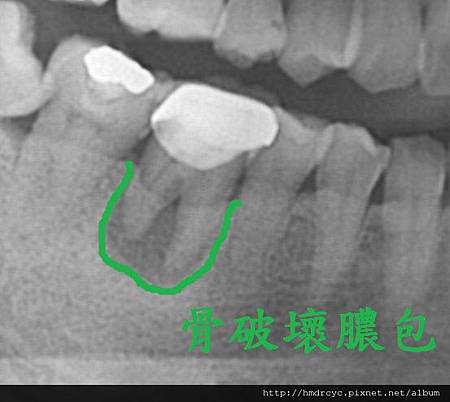

骨頭破壞後原本骨頭位置被發炎的肉取代

甚至形成膿包

根管化膿是原本神經管裡的組織感染

因為上面有牙套 所以就往牙根尖方向蔓延

這會發生在沒有先做根管治療的牙齒

以及根管治療不完全的牙齒

解決方案必須考慮牙套拆除

重新根管治療 甚至牙根尖手術去除膿包

不然有時膿包繼續擴大

會感染到隔壁牙齒甚至形成囊腫